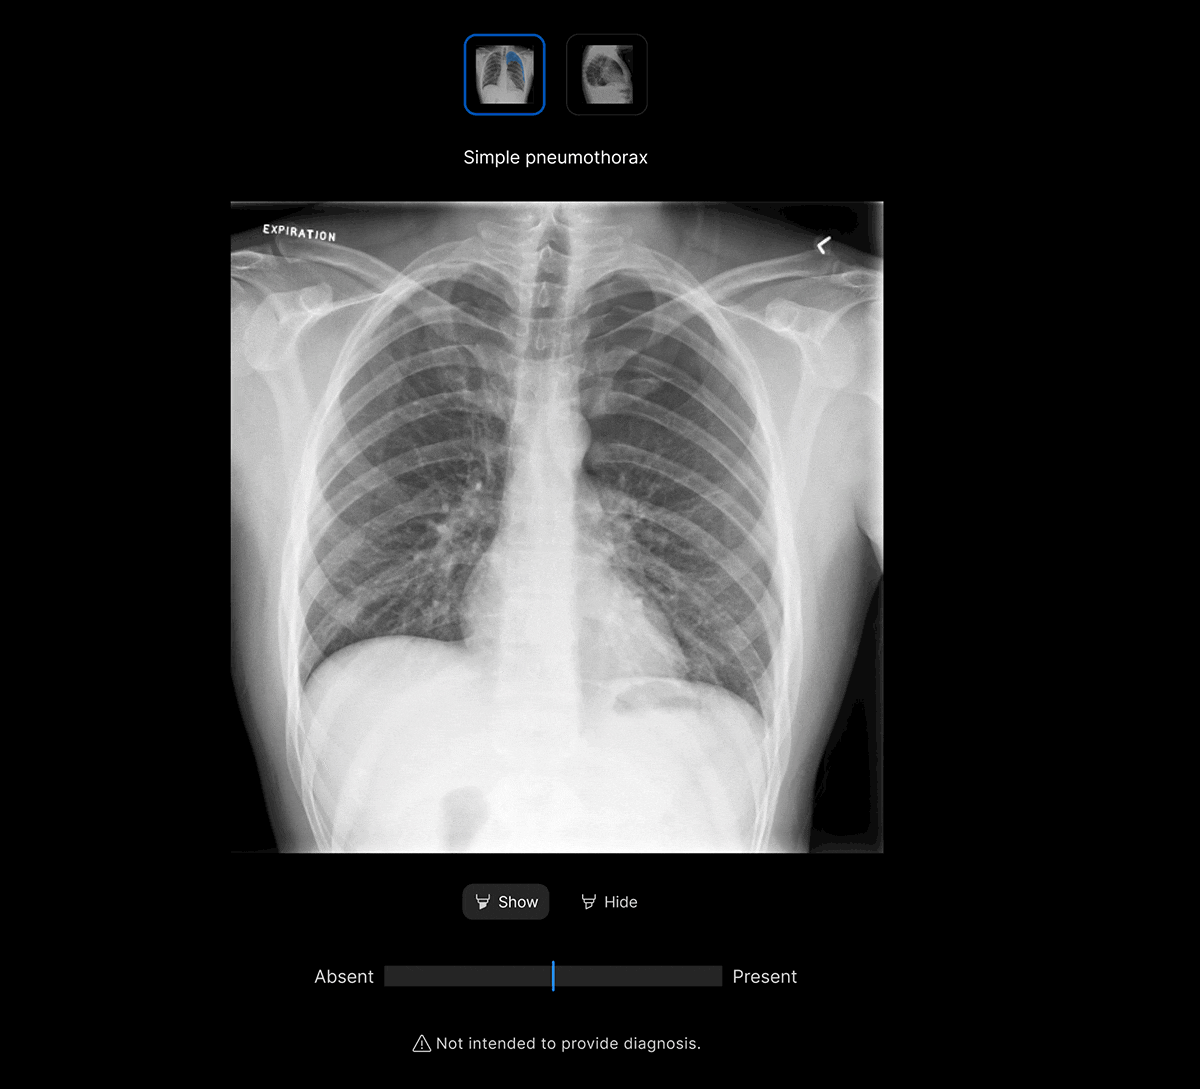

Facilitate accurate diagnoses of complex and subtle cases with AI-decision support identifying up to 124 findings on CXR and 130 findings on CTB.

The user-interface integrates seamlessly with PACS/ RIS, displaying a resizable, no-click overlay window with findings and localisation.

Customisable thresholds for individual findings (to optimise for sensitivity / specificity), to tailor the workflow to your clinical setting or population.

- Explainable AI features such as localisation and a confidence bar to improve AI interpretability and clinical decision making.